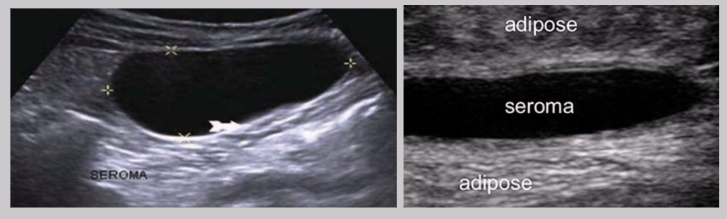

Seroma

Collection of serum in the tissue

Results from a surgical incision or liquefaction of a hematoma

Distinct from hematomas because they contain no red blood cells

US Findings:

Anechoic cystic structure

Well-circumscribed

Posterior enhancement